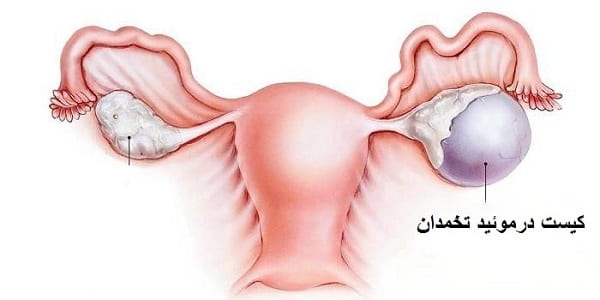

قیمت: 45٬000 تومان - دسته بندی فایل: پاورپوینتدانلود پاورپوینت معرفی کیست درموئید تخمدان

خرید پاورپوینت حرفه ای با موضوع معرفی کیست درموئید تخمدان با قیمت استثنایی از لوکس فایل